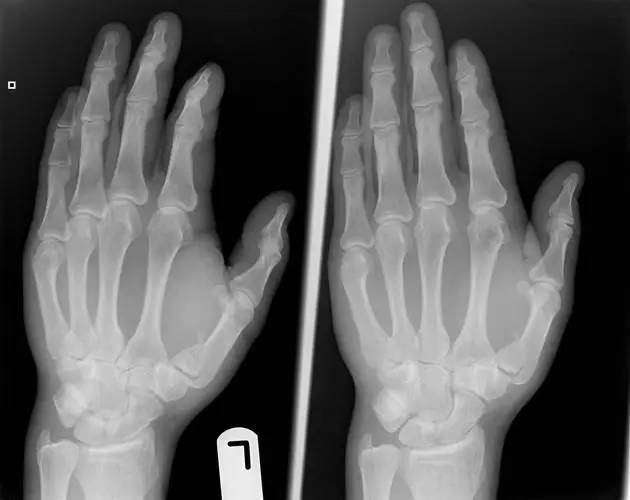

7. Boxer's 骨折

第 5 掌骨颈骨折伴有掌骨头向掌侧移位。

(来源:Radiopaedia)